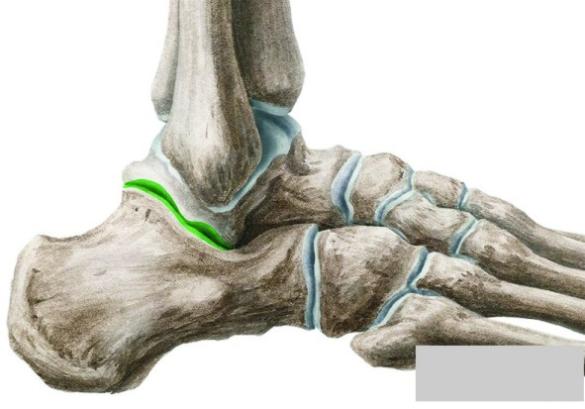

&gornjeg skočnog zgloba ( articulatio talocruralis, slika 3. i 4. )

Slika 3.

Slika 4.